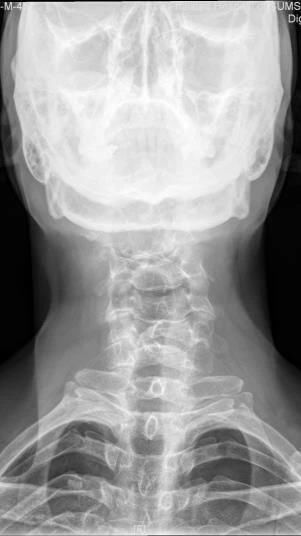

Case12:F,4y;患儿颈部活动受限1个月。